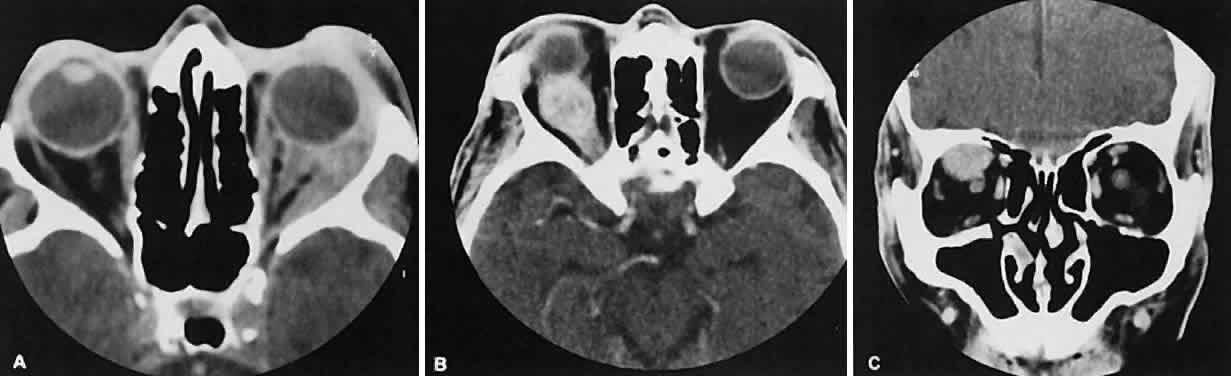

The vascular tumors under consideration are capillary hemangioma, cavernous hemangioma, lymphangioma, and hemangiopericytoma. Capillary hem-angiomas and lymphangiomas are benign infiltrativetumors seen in a pediatric population. Capillary hemangiomas have a homogeneous consistency, display intense uniform contrast enhancement, and do not usually displace any orbital structures (Fig. 12). Phleboliths are a characteristic finding in hemangiomas and, when present, are virtually pathognomonic of this diagnosis.56

Fig. 12. A. Axial view shows an exuberant homogenous soft-tissue mass infiltrating the retrobulbar space and periorbital tissue, typical of large infantile capillary hemangioma. B. Extension (arrow) into the adjacent periorbital tissues can be seen on the coronal view.

Lymphangiomas have a cystic component, which, on occasion, may hemorrhage into itself, accounting for rapid onset of symptoms and clinical/radiographic evidence of mass effect (Fig. 13). In all likelihood, scans require sedation for an adequate study. Thin (1.5-mm) axial views with computer reformatting for coronal views along with contrast enhancement should provide an adequate study.

Fig. 13. Axial view of a lymphangioma that shows a large mixed-density mass with a cystic component.

Both cavernous hemangiomas (Fig. 14) and hemangiopericytomas typically are seen in adults. Their radiographic appearance is similar and shows a well-demarcated, contrast-enhancing mass, although more intense enhancement may be seen with the hemangiopericytoma. The differential diagnosis of a well-demarcated, contrast-enhancing lesion is listed in Table 3.

Fig. 14. Axial (A) and coronal (B) views of a cavernous hemangioma depicted as a hyperdense-enhancing, well-circumscribed mass.